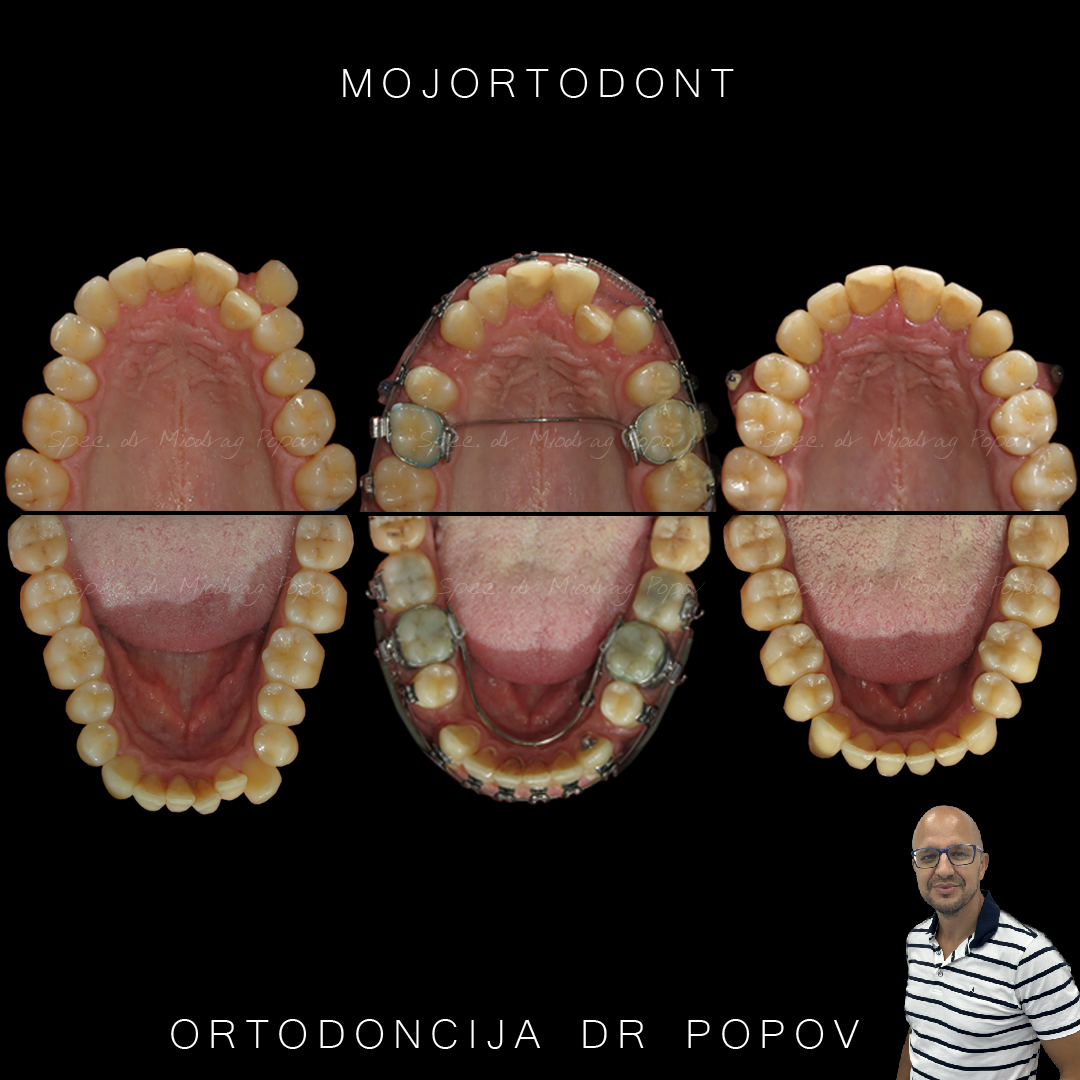

Uspešno završen slučaj ektopičnog očnjaka!

- Ektopičnim očnjakom

- Teskobom u zubnim nizovima, kao i

Kroz precizno planiran i stručno vođen ortodontski tretman, uspeli smo da rešimo sve ove probleme.

Ektopični očnjak je uspečno postavljen na svoje mesto, teskoba je otklonjena, a sredine zubnih nizova su dovedene u savršen sklad.